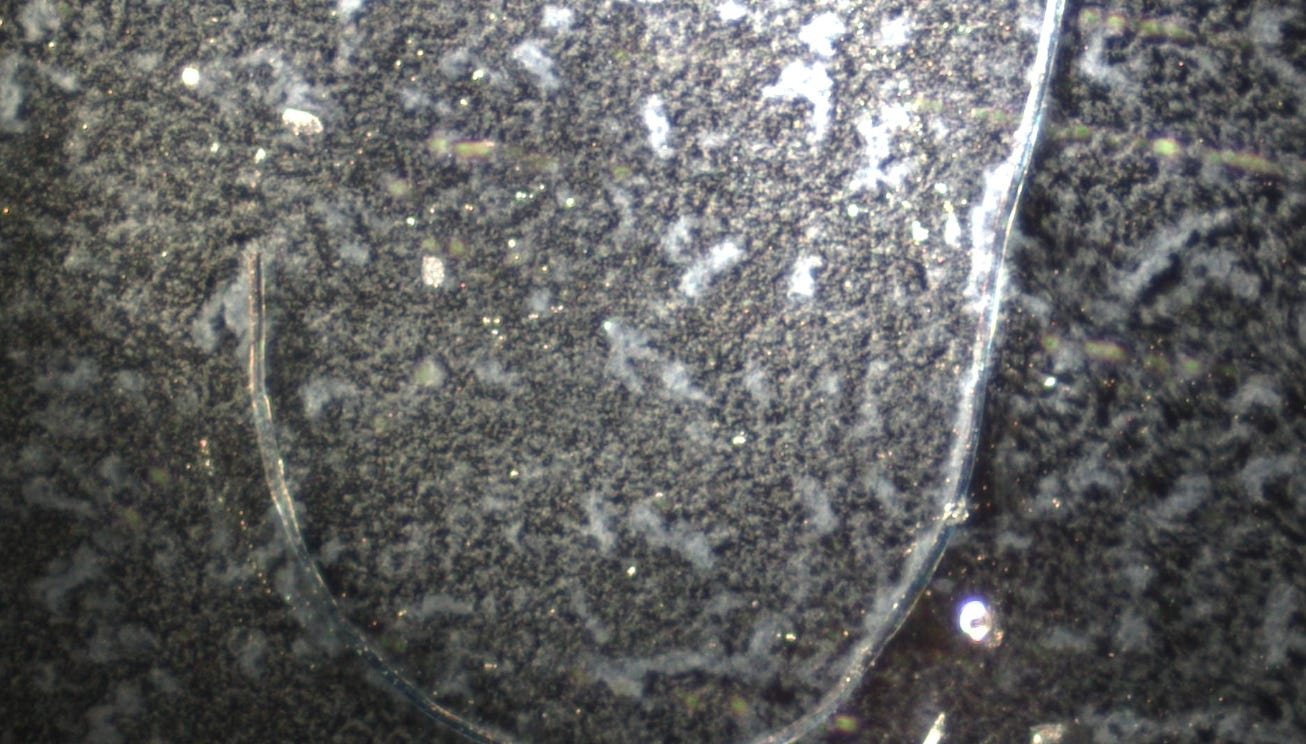

Image: Lantus Insulin mixed with Methylene Blue left overnight After seeing how well Methylene Blue works to prevent the rubbery clot formation, I wanted to test it with the different medications in which I have previously found the hydrogel. I used expired Methylene Blue 1 drop and a drop of Lantus Insulin for this testing.

I had shown before that Lantus has extensive Quantum Dots and hydrogels in it. You can review the Microscopy here: Darkfield Microscopy of Lantus and Humalog Shows Self Assembly Hydrogel I looked at Lantus Insulin first without Methylene Blue. Classic hydrogel background and filament construction was seen.

These are the previous tests I did on Methylene Blue: Also please see the recent effects on the rubbery clots when taking it orally: Methylene Blue Prevents Rubbery Clot Formation, Essential Oils Help Too – Experiment Documentation Then I mixed a drop of Lantus Insulin with Methylene Blue and this is what it looked like, similar to before with Budesonide: After a couple hours these blue streaks had formed under the cover slip

I left the slides overnight. The hydrogel had migrated around the Methylene Blue under the cover slip, as if it was magnetically attracting it.